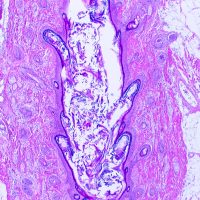

左上の写真で見えるのは,腫瘍内部にあった小脳組織です。内胚葉,外胚葉性組織など多様に分化した組織が混入しています。

乳児の先天性奇形腫は手術摘出だけで治療できる良性の腫瘍です